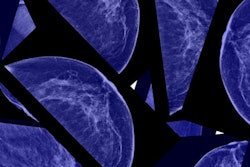

Using the model, the researchers analyzed macroeconomic costs for 29 different cancers across countries and territories. They found that these aggregate costs amounted to $25.2 trillion at constant 2017 prices. It also found that the five cancers with the highest economic costs are those related to the trachea, bronchus, and lung (15.4%); those related to the colon and rectum (10.9%); breast cancer (7.7%); liver cancer (6.5%); and leukemia (6.3%).